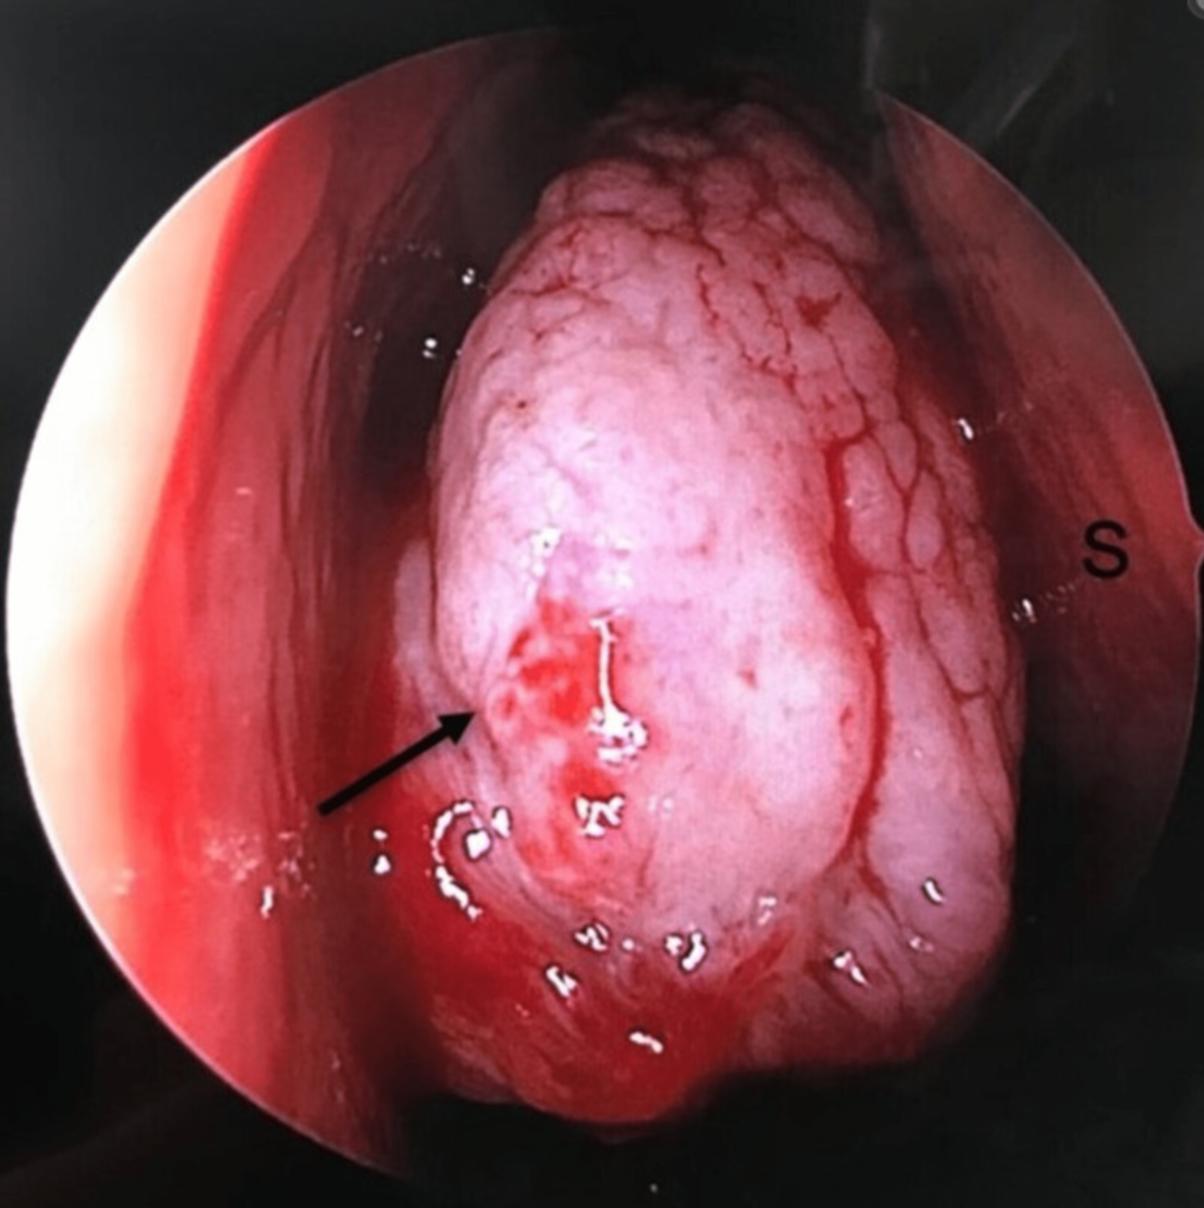

患者术后恢复良好。在三个月的随访中,患者无明显不适,鼻内镜检查未见复发的、迹象(图4)。

图4